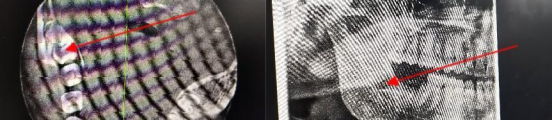

阻生牙微创拔除术

现代根管治疗术